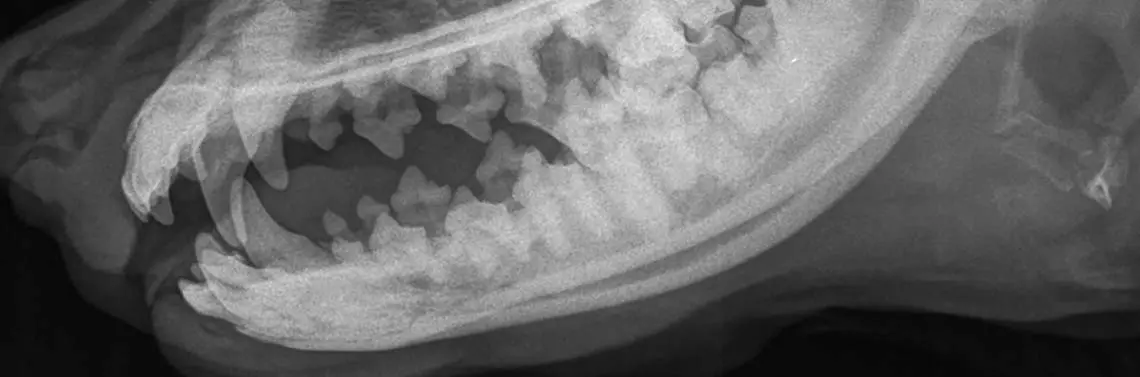

Fot. 2 Zdjęcie rentgenograficzne (RTG) w projekcji strzałkowej

Fot. 3 Zdjęcie rentgenograficzne (RTG) w projekcji bocznej

Wykonano zdjęcie rentgenograficzne (RTG) w projekcjach bocznej oraz strzałkowej (fot. 2 i 3). Radiogramy uwidoczniły mineralizację w okolicy odpowiadającej umiejscowieniu przewodu ślinianki przyusznej. Zwierzę poddano również sjalografii (fot. 4).